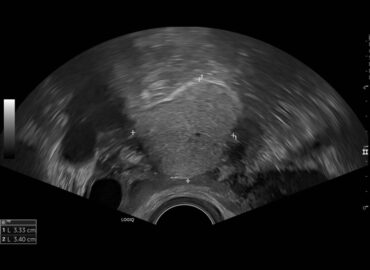

46 años. Control ginecológico